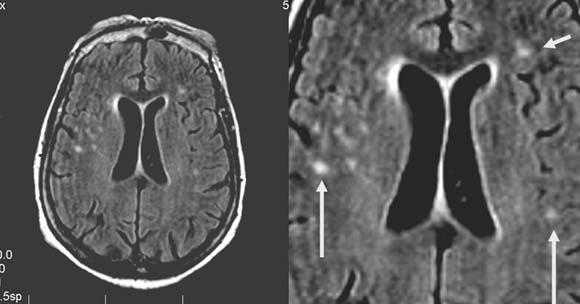

Внутримозговая гематома (граница острой и ранней подострой стадий - 3 суток), осложнившаяся внутрижелудочковым кровоизлиянием.

Внутримозговая гематома, поздний подострый период (14-21 день) с перифокальным отеком вокруг гематомы.

Внутримозговая гематома правой теменной доли. Граница поздней подострой и ранней хронической стадии. В Т2-ВИ виден ободок гемосидерина (стрелка).

Хочется подчеркнуть возможность МРТ в выявлении последствий геморрагического поражения - остается хорошо дифференцируемый по Т2 ободок гемосидерина, недоступный для визуализации при других методах нейровизуализации.

Стрелками показан ободок гемосидерина по периферии постишемической кисты.